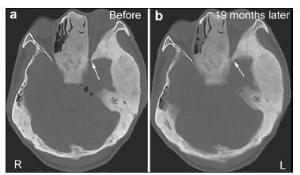

20161117200932  Figure 1 (a, b) A computed tomography (CT) scan demonstrating the expansion of multiple skull bones. The involved bones present with various appearances of mixed radio-dense/radio-lucent lesions, which can be described as “ground-glass”, “lytic”, and “cystic”. Left: Axial CT cisternography demonstrates a fistula at the posterior wall of the right frontal sinus (white arrow). The density of both frontal involved bones is slightly lower than for other skull bones. Right: A coronal CT scan demonstrates pneumocephalus in the right frontal lobe (black arrow).